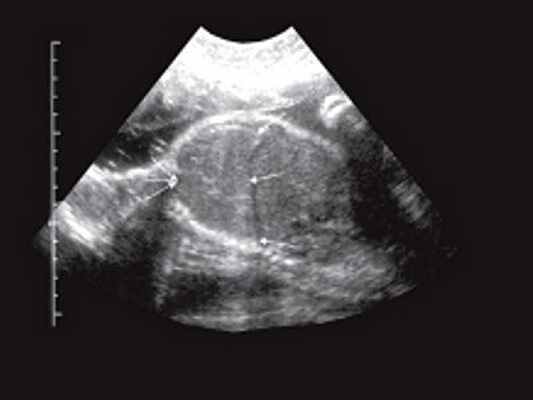

а) Опухоль в стенке прямой кишки и клетчатке на уровне предстательной железы. Слева от опухоли в клетчатке увеличенный гипоэхогенный лимфатический узел.

б) Опухоль на уровне семенных пузырьков. Изображение перевернуто, цифры 6 и 12 обозначают положение датчика по отношению к передней (12 часов) и задней (6 часов) стенкам прямой кишки.

в) Опухоль на уровне семенных пузырьков.

1 - стенка кишки; 2 - опухоль; 3 - параректальная клетчатка; 4 - надкостница крестца; 5 - слизистый слой кишки.

При трансректальном ультразвуковом исследовании (ТРУЗИ) датчик был проведен на 15 см от анального канала, были осмотрены стенки прямой кишки и параректальная клетчатка. Установлено, что анальные сфинктеры обычной структуры. На высоте 4 см от ануса преимущественно по задней стенке определялась опухоль (рис. 1а) 5,2х4,0х7,0 см низкой эхогенности с мелкоточечными множественными гиперэхогенными включения ми. Контуры опухоли неровные, границы нечеткие. Слизистая оболочка прямой кишки в зоне опухоли не изменена, представлена гиперэхогенным слоем. Отмечалась выраженная инфильтрация опухолью параректальной клетчатки, доходящая практически до надкостницы крестца (рис. 1 б, в). Наряду с этим в непосредственной близости от основной опухоли в параректальной клетчатке определялись гипоэхогенные образования с неровными контурами, которые были расценены как депозиты опухоли (см. рис. 1а). Кроме того, в параректальной клетчатке вы явлены два гипоэхогенных образования округлой формы с ровными четкими контура ми 1,4х1,3х1,4 и 1,0х1,0х1,1 см, которые представляли собой увеличенные лимфатические узлы. Дано заключение о наличии опухоли прямой кишки, исходящей из ее внутренних слоев, прорастающей до надкостницы крестца.